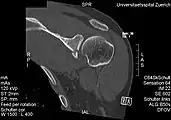

Bankart lesion

The glenoid labrum, labeled glenoid ligament, is damaged in a Bankart lesion. Lateral view demonstrating the articular surface of the right scapula is shown.